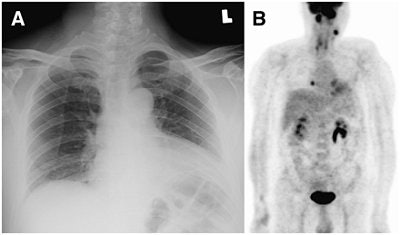

| A 49-year-old man who was a patient with NPC of stage T4 N2. (A) Chest radiography revealed no evidence of chest metastasis. (B) Maximum intensity projection image of F-18 FDG-PET revealed focal metastasis in right lower chest. CT-guided biopsy of 0.8-cm nodule in right lower lung confirmed it to be a metastatic tumor. "18-F-FDG PET Can Replace Conventional Work-up in Primary M Staging of Nonkeratinizing Nasopharyngeal Carcinoma" (Journal of Nuclear Medicine, Vol. 48:10, pp. 1614-1619). Reprinted by permission of SNM. |